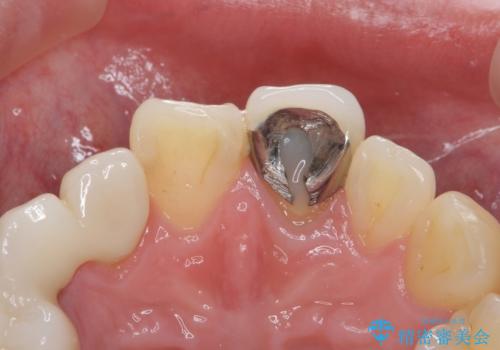

- 前歯の被せ物のやり替えを希望して来院されました。

再根管治療の後、審美性の良いジルコニアクラウンをセットしていきます。